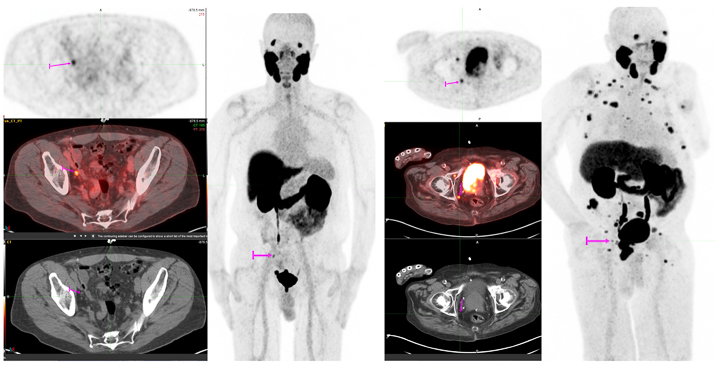

Our Nuclear Medicine and Cancer and Molecular Imaging Divisions are excited to announce the roll-out of our newest PET tracer, 18F-PSMA for prostate cancer PET/CT imaging with Shields Health Care Group. This new tracer is addressing an umet need in prostate cancer care and can detect substantially more prostate cancer lesions compared to conventional imaging. These high-quality exams are allowing us to find small sites of disease and providing clinicians with the information they need to make treatment decisions. The figures show examples of how this tracer is able to detect metastatic disease in 4 mm (left) and 6 mm (right) lymph nodes, that would otherwise not meet pathologic size criteria by CT.

Images provided by Lacey McIntosh, DO, MPH, Division Chief Oncologic and Molecular Imaging, Department of Radiology, UMass Chan Medical School.